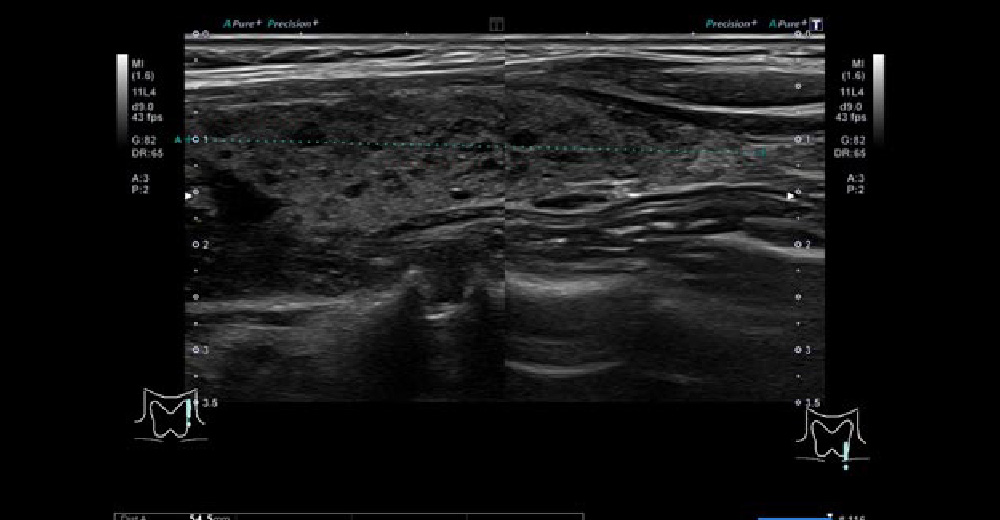

背景甲状腺はいわゆる“粗雑”で、ぱっと見、すかすかしています。 悪性リンパ腫 を合併することもあり、生涯にわたって注意が必要です。

橋本病